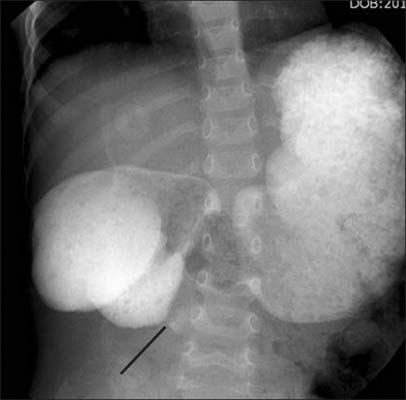

Fig. 2

Upper gastrointestinal series showed partial obstruction in 2nd portion of duodenum with abrupt narrowing caused by web (line).

Fig. 2 Upper gastrointestinal series showed partial obstruction in 2nd portion of duodenum with abrupt narrowing caused by web (line).